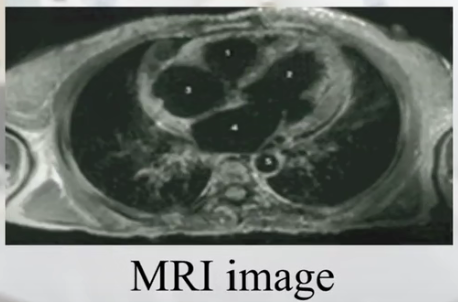

(7)MRI(RF、核磁共振)图像:

(2)MRI(核磁共振)图像: 清晰看到除了骨结构之外的一些软组织,更能描述人体软组织结构。